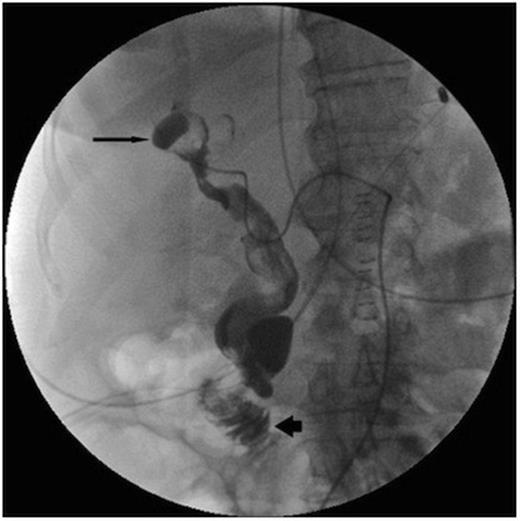

Post operatively the upper gastrointestinal bleeding continued. A second urgent OGD endoscopy showed more blood clots and fresh blood in the fundus, but once again no source for the bleeding was seen. Once the patient was stabilised an angiogram was performed. This showed a 1cm pseudoaneurysm of the right hepatic artery in the right lobe close to the Porta Hepatis. The pseudoaneurysm arose from the anterior branch of the right hepatic artery and communicated with the bile duct. The 2nd part of the duodenum was opacified, showing haemorrhage from the lesion into the duodenum via the bile duct (Figure 1).